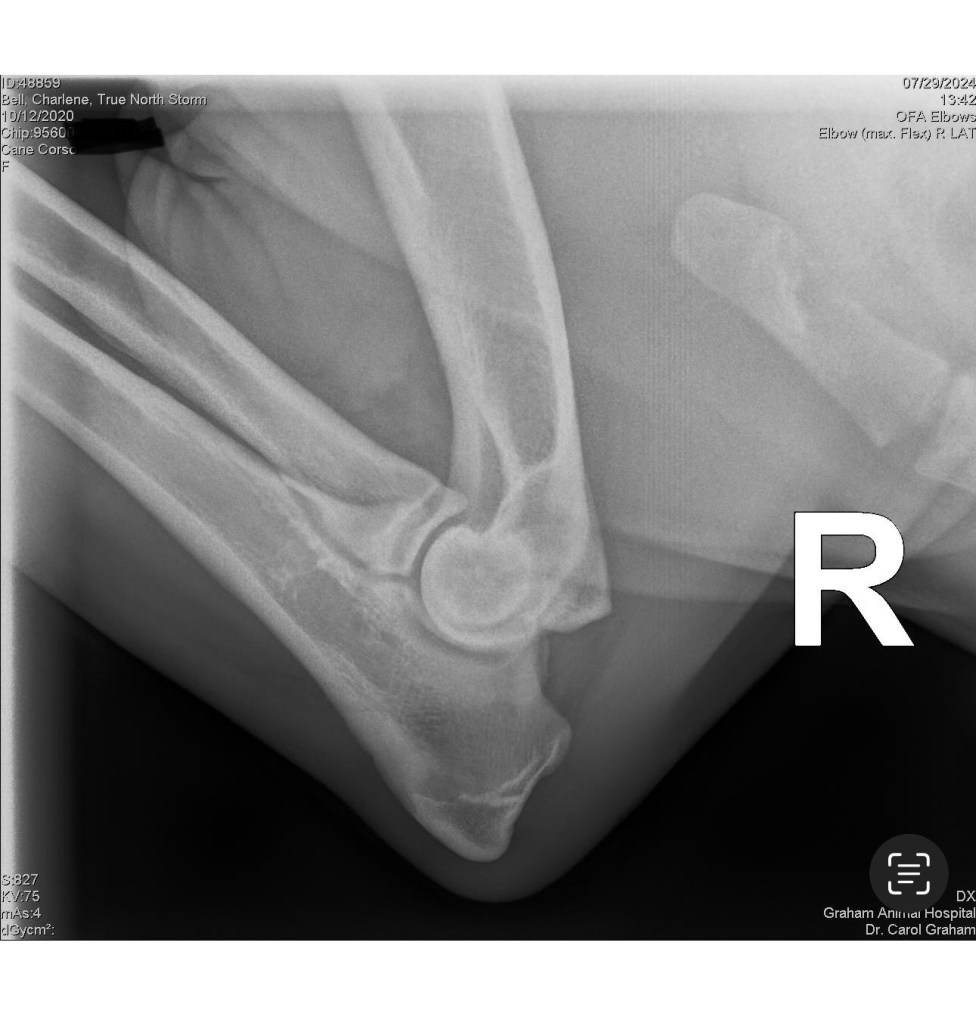

Storm has had OFA elbows, PennHip, and DSRA testing completed. Her registrations include CKC, AKC and ICCF.